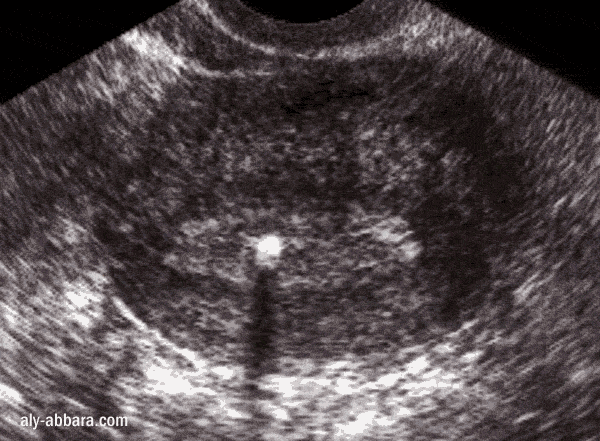

L'emplacement dans l'utérus vu par l'échographie

La tige (branche verticale) du stérilet (coupe transversale sur l'utérus)